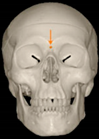

Three points determined the Acta plane: O, F right (FR), and F left (FL) (Table 2). Point O is the midpoint between the most craniodorsal point of the dorsum Sella and the most posterior dorsal point of the Basion in the midsagittal plane (Figure 1). Both points F are a result of the intersection between two lines: the line that connects the most inferior points of the lower orbital margins, right and left, and a line perpendicular to this line that runs through the most external points of the orbital margins, right and left (Figure 2). The new transverse reference plane, the Acta plane (Figure 2), is created by connecting the O-point (Figure 1) with FR and FL (Figure 2).

Figure 1.

Point O (green dot) is the midpoint between the dorsum Sella (Se) (red dot) and the Basion point (Ba) (yellow dot).

Figure 2.

(A) Construction of the F-points (right and left), frontal view. The F-points are originated from the intersection between the line connecting points A (the most inferior point of the lower orbit) and the perpendicular line to it that passes through points B (most external/lateral point of the Orbita). (B) Transverse view of the ACTA plane.